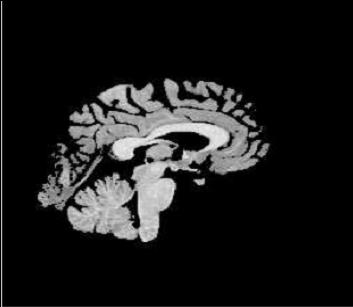

| template | coarse deformed template | fine deformed template | target | |